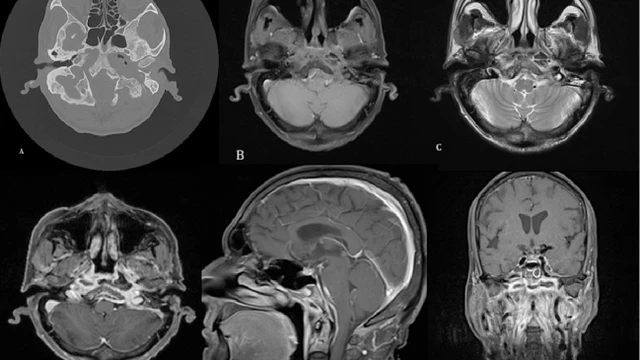

Viêm xương hàm là một bệnh lý xảy ra khi có sự bất ổn ở khu vực khớp hàm và các khớp cơ xung quanh. Bệnh này không chỉ gây đau hàm thường xuyên, mà còn làm co thắt các cơ, làm mất cân bằng trong hệ thống xương sọ và xương hàm. Viêm xương hàm ảnh hưởng trực tiếp đến quá trình sinh hoạt hàng ngày, đặc biệt là khi nói chuyện và nhai nuốt thức ăn.